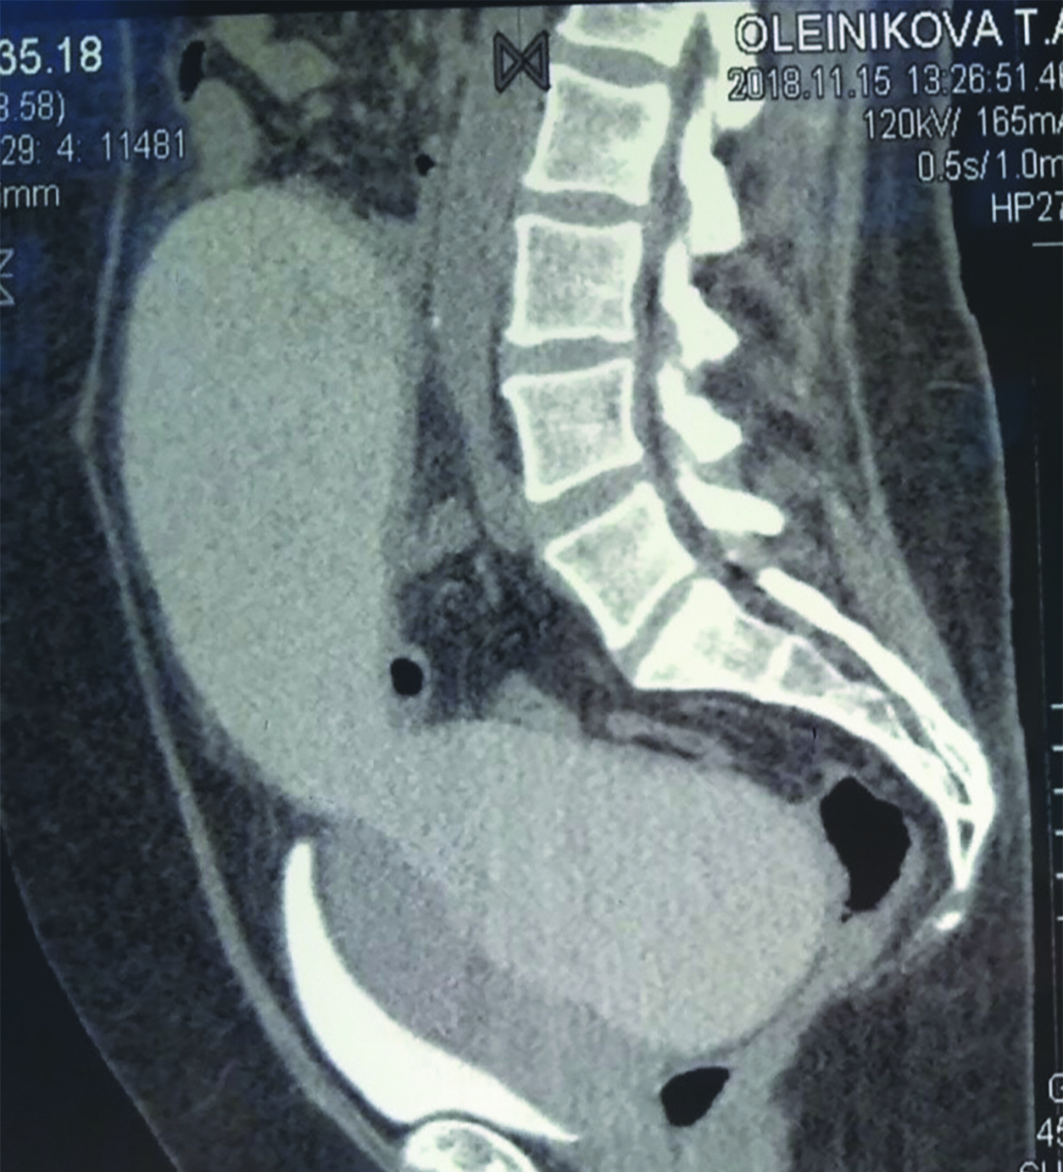

Лабораторные исследования крови выявили умеренное повышение содержания лейкоцитов до 14х109. Биохимический показатели в норме. КТ с контрастом подтвердило наличие жидкостного образования в забрюшинном пространстве аналогичного размера без накопления контрастного вещества (рисунок 1).

Рисунок 1. Компьютерная томограмма больной О., 51 год. Гигантский мочевой затек в забрюшинном пространстве (боковая проекция).

Figure 1. Computer tomogram of patient O., 51 years old. Giant extravasation of urine in the retroperitoneal space (lateral projection).